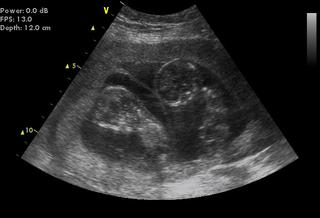

Jinak já jsem po 1. IVF, už 7. den od ET jsem měla //, minulý týden na UTZ potvrzeny dvě bublinky, dneska jsem 5tt+4 a už se do ničeho nevejdu - mám dojem, že s dvojčátkama bude všechno mnohem intenzivnější a rychlejší 😀

Tak hlásím screening NEGATIVNÍ ufff 🙂 mimča maj A 69,3 a B 70,00mm odpovídaj 13+2tt,srdíčka krásně tloukla, kůstka přítomná, projasnění 1,60 a 1,50mm, takže celkem výsledek negativní ale prej komplet výsledky se dají říct až s odběrem krve ve 2. trimestru... takže jsem už objednaná na 21.10. na krev a pak na konzultaci se všemi výsledky...

ale pláču 😢 zase nemám fotku v tom " blbým" Gennetu, fotky vydávaj sestry na recepci, kde si z počítače vyberu kterou chci, což by bylo super, kdyby mě tam našly...zkoušela tam zadávat jména, rč a prostě já jim tam neexistuju, přesto, že doktorka to tam prej zadávala normálně a i zprávu mi dala normálně s mojím jménem... a to by byla tak krásná fotka, bobánci tam seděli jak v autobusu úplně stejně za sebou, no hrozná prča, byli tam jak přes kopírák hlavičkama nahoru ručičky před sebou 🙂 manžel mě uklidnoval, že to není tragédie, to já vím ale oni byli tak kouzelní...

tak v Gennetu asi viděli ten můj zoufalej výraz, že nemám obrázek, tak hledali a hledali až našli 😀 a před chvilkou mi přišel fotka mailem,nevybrala sice nejhezčí ale aspoň něco… 😉